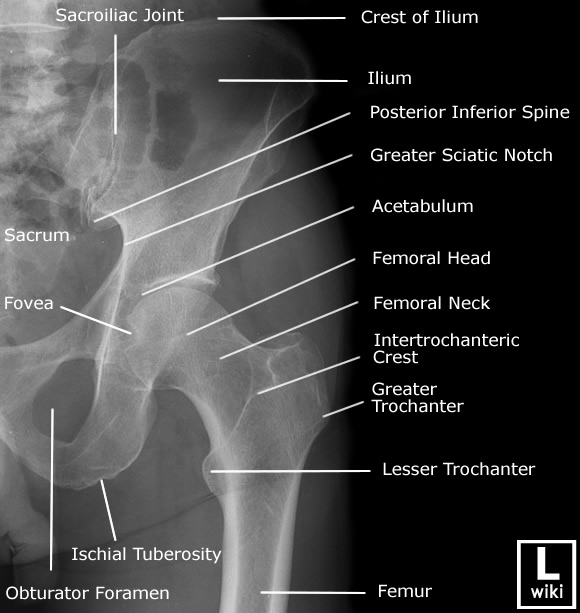

| [Anatomy] Hip joint(고관절) (0) | 2024.01.29 |